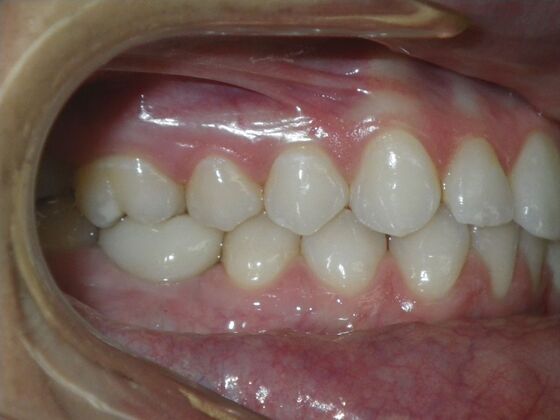

Invisalign: Case 17

This patient was an awesome dental assistant for our practice and we were all very sad when she had to move closer to her home. She was very interested in correcting some minor spacing and rotations in her upper and lower anterior teeth and to decrease her overbite as well.Treatment took about 12 months, but we were pleased with the results and fabricated clear invisalign vivera retainers. We are still hoping one day she will return to be with us again.